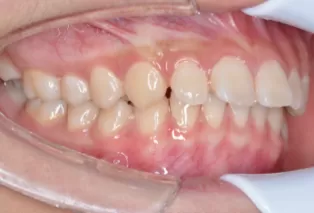

Intraoral photos after treatment